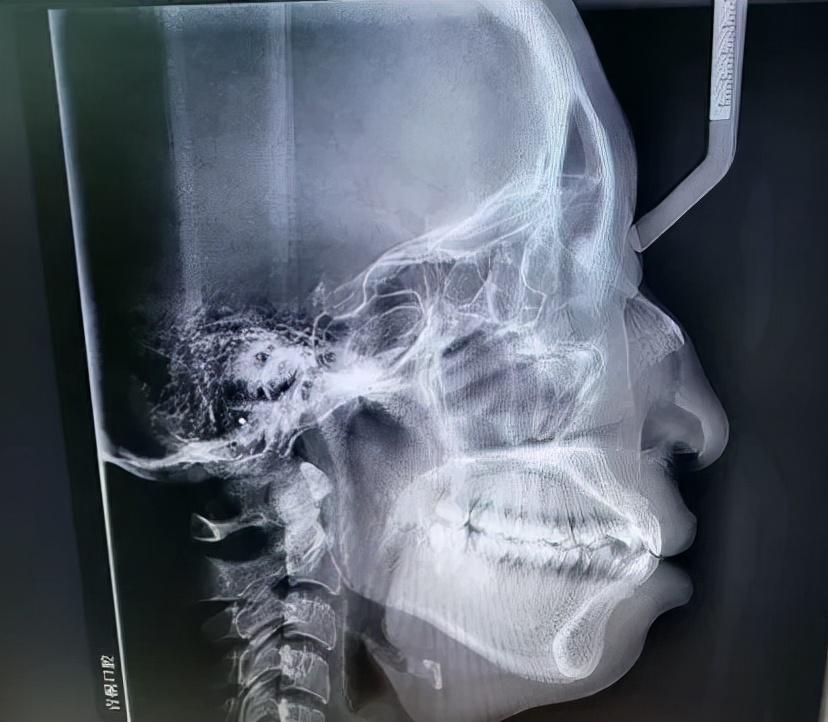

如何判斷是否屬于骨性口凸,不是光看照片或是照鏡子就能判斷的,必須要拍片檢查,通過專業(yè)的頭影測量數(shù)據(jù)才能知道。骨性外凸通常包括以下幾種具體情況。

1、上頜骨發(fā)育過度:上頜骨過度發(fā)育導(dǎo)致凸嘴。2、下頜骨發(fā)育不全:很多人認(rèn)為骨性嘴凸一定是上頜骨突出造成的,但也不一定,也有一些人的嘴看起來很凸,是因?yàn)橄骂M骨發(fā)育不全(即下頜骨后縮)。3、雙下巴問題:當(dāng)然還有一種情況是上下頜骨都有問題,這也是比較常見的一種情況,比如上頜骨突出,下頜骨發(fā)育不全(下頜骨后縮),看起來就像嘴巴突出和沒有下巴的結(jié)合體。